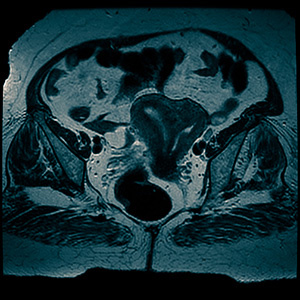

В клинике МРТ диагностики «МедСевен» вас готовы принять в любое время суток. Опытный врач выполнит первичный осмотр и даст вам направление на магнитно-резонансную томографию. Этот вид диагностики считается наиболее точным из всех существующих. Мы выполняем его на мощном томографе Philips Intera 1,5 Тесла. Результатам обследования доверяют ведущие врачи в Германии, Израиле и США. Это связано с тем, что в нашей клинике трудятся лучшие профессионалы в Москве.

Мы рекомендуем делать именно МРТ, поскольку это самый информативный способ диагностики. Он безопасен, выполняется за 15-20 минут, дает наиболее полную картину состояния здоровья. Кроме того, каждый клиент нашей клиники получает скидку в 50 % на консультацию специалиста для назначения дальнейшего лечения. Записаться на прием вы можете прямо сейчас в режиме онлайн непосредственно на нашем сайте.